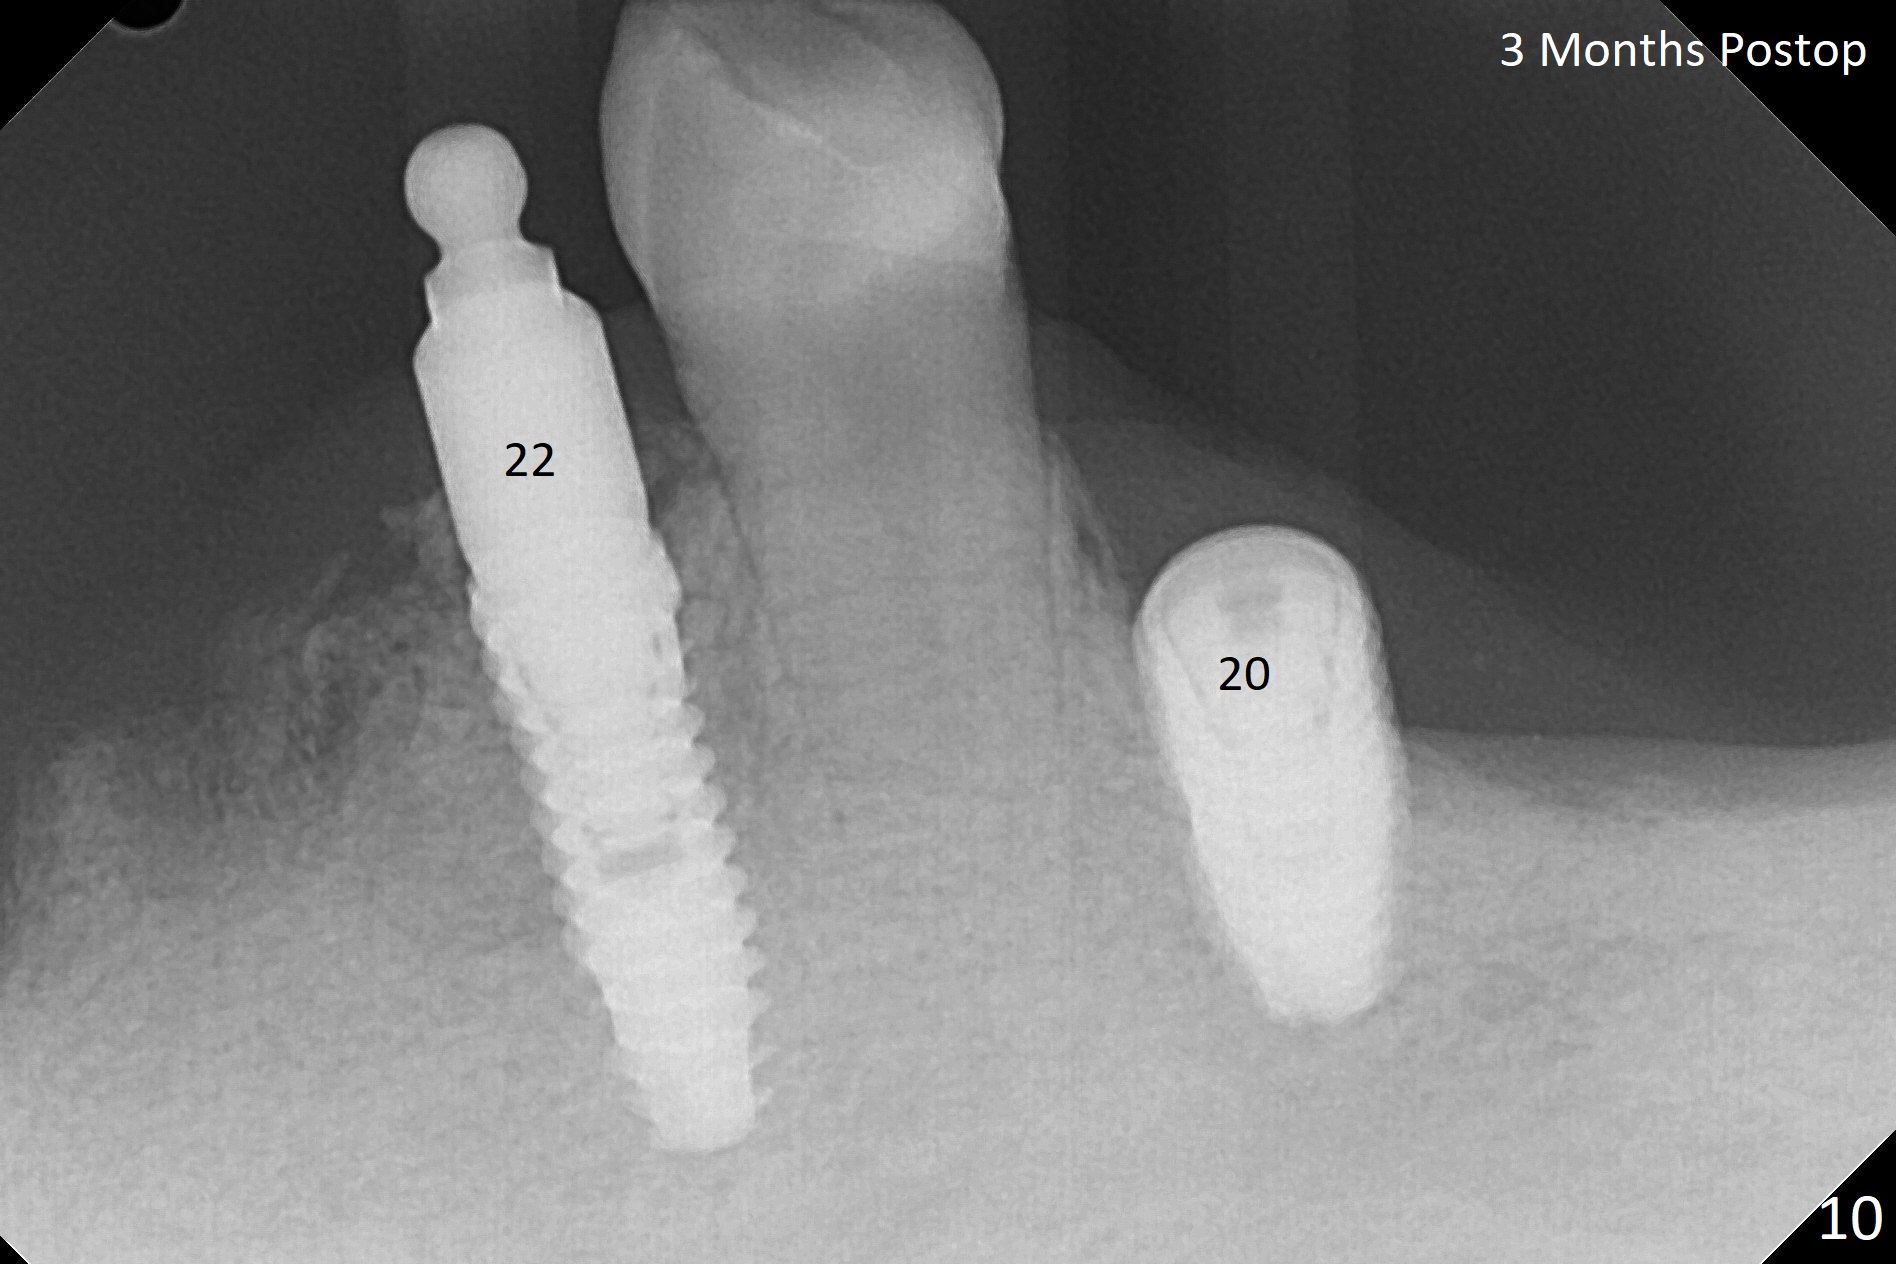

Three months post socket preservation (with buccal plate loss previously), a 3.5x11.5 mm implant is placed at #27 subcrestal (Fig.1). When implants are placed at #22 and 20 (Fig.2,4), threads are exposed buccal (B). Mixture of autogenous bone and allograft is placed to cover the exposed threads (Fig.3,5) following deep placement at #20. For safety, the implant at #20 is buried. Pain control at #18 is poor when initial osteotomy is being established (Fig.6 *), as related to severe infection. Repeated block anesthesia allows to finish implant placement with primary stability; a 3.5x2 mm ball abutment is placed (Fig.7). With placement of 2 other ball abutments at #27 and 22 (Fig.3), the lower existing RPD is converted to a removable provisional (Fig.8). With addition of acrylic, the socket of #20 is covered (Fig.9). There is no apparent bone #20 distal 3 months postop (Fig.10,11 <). Re-graft is needed? The implant at #21 appears immediately subgingival 5 months postop (Fig.12 *). The distobuccal threads are exposed (Fig.13). After decortication, allograft is placed, followed by 6-month membrane. In fact, a shorter and smaller implant should be placed instead. The patient has to wear the RPD for mastication. It would be more painful without it. Later the tissue surface of the RPD is trimmed.